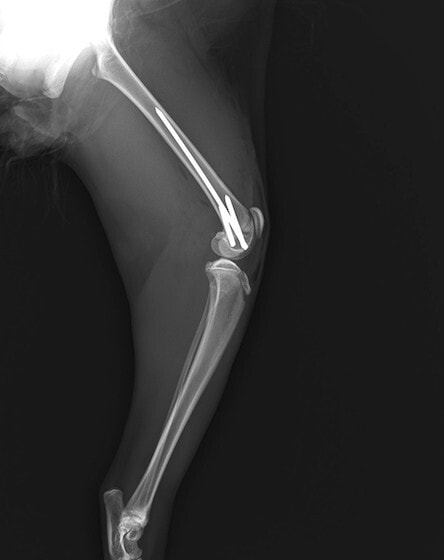

症例3:キルシュナーワイヤーのピンニングによる整復

ペルシャ猫 11ヶ月齢 雄

他院にて左大腿骨遠位の成長板骨折(salter-harrisⅠ型)が認められており、治療相談を目的として来院。当院にて、キルシュナーワイヤーを用いたピンニングにより骨折部位の整復を行いました。術後の経過は良好で、現在も経過観察中です。

術後レントゲン

Arthrex社のターゲティングデバイスを用いてピンニングの位置を調整することで、確実な固定を行っています。当院ではこの手術器具以外にも、人の手術にも使用される様々な器具を導入し、手術精度を高め、また医療メーカーと新しい器具の開発、試作にも取り組んでおります。